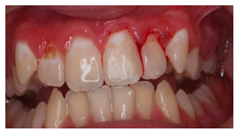

The question from scenario 1a was open-ended; participants were asked to provide a diagnosis of a lesion in tooth 3.6. A total of 41.5% of the surveyed students considered that the image presented a retentive pit/fissure or stained pit/fissure; 39% of them answered that the image exhibited a carious lesion. The answers “healthy”, “early carious lesion”, and “chronic carious lesion” were less frequent: 2.4%, 9.8%, and 7.3%, respectively. For this question, the correct answers were: “retentive pit/fissure or stained pit/fissure” and “chronic carious lesion”. “Healthy” and “carious lesion” were considered as incorrect. Thereby, 48.8% of the surveyed students answered correctly (Figure 1).

For scenario 1b, students were required to order different complementary diagnostic tests from more to less adequate for the diagnosis of the presented case. The most prevalent answer, “bitewing X-ray” (51.2%), “periapical X-ray” (12.2%), and “no complementary diagnostic test is required” (36.6%). The latter was the option considered as correct (Figure 1).

In a similar manner, the surveyed students were asked to order different therapeutic options in scenario 1c. The option “oral health instructions and 6-month follow-up visit” was selected by 51.2% of the participants. This answer was considered as correct Additionally, 9.8% of the students would perform a “pit and fissure sealing”, 7.3% would opt for a “2-year follow-up visit”, and 2–4% would carry out a resin-based obturation/filling (Figure 1).

The results from the present study confirmed that approximately half of the last-year students from the degree in dentistry proposed a correct diagnosis for the first clinical scenario, following the criteria established by The International Caries Consensus Collaboration or ICCC [33], in which the extension and activity of the lesion are considered. The question was open-ended, and a high percentage of participants answered “caries”, without providing more details regarding the activity of the lesion.

As advised by the ICCC, the diagnosis of caries, nowadays, has to be based on the visual clinical exploration and the evaluation of individual risk of caries development [34]. Diagnostic tests will act as supporting material for the determination of the extension of the lesion and to control its progression over time. The majority of students selected, as a complementary test, performing a bitewing X-ray to confirm de diagnosis. This could be considered as an indication for “overdiagnosis”, as this test, in the case of an inactive carious lesion limited to the superficial enamel on the occlusal surface, does not provide any additional help to the diagnosis [13]. This tendency to use complementary tests could be explained by the clinical inexperience of the students and by the excessive trend to support diagnosis on complementary tests (Figure 1).

Currently, there is a great tendency towards the restoration of lesions limited to the enamel, although the scientific evidence supports other non-invasive alternatives for the control of these lesions [35]. According to these criteria, an inactive carious lesion categorized as ICDAS II (clinical scenario 1c) should not receive any restorative treatment, but only require oral health instructions and control of individual risk factors, together with follow-up control visits [35]. Interestingly, the percentage of students who correctly answered the therapeutic approach in scenario 1c (51.2%) was higher than those who correctly answered the diagnosis in scenario 1a (48.8%). This difference may have been due to the fact that students who misdiagnosed scenario 1a as “healthy” or “early carious lesion” may have selected “oral health instructions and 6-month follow-up visit” as a therapeutic approach. However, a little more than half of the students selected this non-invasive therapeutic alternative. It should be highlighted that up to 41.7% of the students would place a resin composite restoration, which in this case is considered as an “overtreatment”. Available systematic reviews among the literature regarding the treatment for early carious lesions found a significative proportion of dentists who would propose restorative treatments upon carious lesions for which minimally invasive technique are indicated [30,32]. Thus, it is necessary to orient dental students into a less invasive approach, taking into account the natural progression of the disease, and treating lesions according to their extension and carioactivity. Because the influence of the type of undergraduate formation influences the postgraduate therapeutic attitude [36].